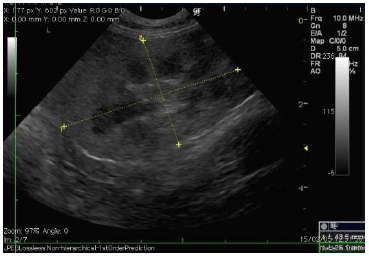

腎臓の超音波(エコー)画像です。

左が正常な腎臓、右が今回の猫の腎臓です。 真ん中の黒い部分が広がっていますが、これは結石によって先へ流れなくなってしまった尿が腎臓に溜まっているためです。 この状態が進行するほど、腎臓の機能は失われていきます。

上が正常な腎臓、下が今回の猫の腎臓です。 真ん中の黒い部分が広がっていますが、これは結石によって先へ流れなくなってしまった尿が腎臓に溜まっているためです。 この状態が進行するほど、腎臓の機能は失われていきます。 |